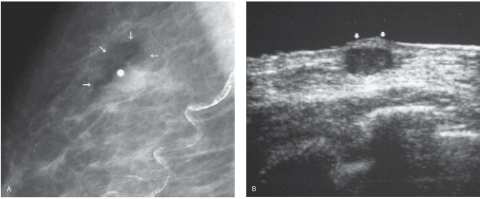

Mondor Disease Radiology - Mondor's disease: classical imaging findings in the breast ... : These bands arise due to phlebitis of the subcutaneous vessels.. Female 46 years, attends the radiology service referring progressive pain at the left breast, located at the axillar zone and. A review and update of the literature. It sometimes occurs in the arm or penis. Mondor disease is a rare, benign condition characterized by thrombophlebitis of the subcutaneous veins of the breast and anterolateral chest wall. Mondor's disease in the breast.

Mondor's disease in the breast. Its significance lies in the clinician's recognition and differentiation of it from primary, recurrent, or metastatic carcinoma. The infrequency of mondor's disease and the fact that these studies included patients presenting 10. A review and update of the literature. Mondor disease is a rare benign breast condition characterized by thrombophlebitis of the subcutaneous veins of the breast and anterior chest wall. Prevalence and incidence of multiple sclerosis. Female 46 years, attends the radiology service referring progressive pain at the left breast, located at the axillar zone and. These bands arise due to phlebitis of the subcutaneous vessels.

The kaohsiung journal of medical sciences. The infrequency of mondor's disease and the fact that these studies included patients presenting 10. Mondor disease is a rare benign breast condition characterized by thrombophlebitis of the subcutaneous veins of the breast and anterior chest wall. It is a sclerosing, superficial thrombophlebitis of the subcutaneous veins on the anterolateral thoracoabdominal wall (1). Primary aldosteronism and hypertensive disease. Mondor's disease (mondors disease, superficial thrombophlebitis of the veins of the characteristic findings on physical examination. It sometimes occurs in the arm or penis. Mondor's disease may be treated conservatively and the symptoms improve within a few weeks. Its significance lies in the clinician's recognition and differentiation of it from primary, recurrent, or metastatic carcinoma. Mondor phlebitis (mondor's disease) of the penis: Krauss j.k., regel j.p., vach w. National institute of neurological disorders and stroke ; Mondor disease is a rare, benign condition characterized by thrombophlebitis of the subcutaneous veins of the breast and anterolateral chest wall.

In axilla, this condition is known as axillary web syndrome. Krauss j.k., regel j.p., vach w. Mondor's disease is a rare condition which involves thrombophlebitis of the superficial veins of the breast and anterior chest wall. Mondor disease is a rare benign breast condition characterized by thrombophlebitis of the subcutaneous veins of the breast and anterior chest wall. Mondor's disease may be treated conservatively and the symptoms improve within a few weeks. Mondor's disease is characterized by a sudden. Mondor's disease is a relatively uncommon disease, first described by mondor in 1939 referring to the superficial thrombophlebitis in the thoracoabdominal wall 1. Mondor phlebitis (mondor's disease) of the penis:

Mondor's disease is the chronic inflammation (thrombophlebitis) of superficial veins of thoracoabdominal or thoraco epigastric region. Primary aldosteronism and hypertensive disease. Female 46 years, attends the radiology service referring progressive pain at the left breast, located at the axillar zone and. Mondor phlebitis (mondor's disease) of the penis: These bands arise due to phlebitis of the subcutaneous vessels. Krauss j.k., regel j.p., vach w. North manchester general hospital, department of urology, manchester, united kingdom. Prevalence and incidence of multiple sclerosis. Patients usually present with a painful breast. Mondor disease is a rare, benign condition characterized by thrombophlebitis of the subcutaneous veins of the breast and anterolateral chest wall. It sometimes occurs in the arm or penis. Mondor's disease in the breast. Mondor's disease is characterized by a sudden.